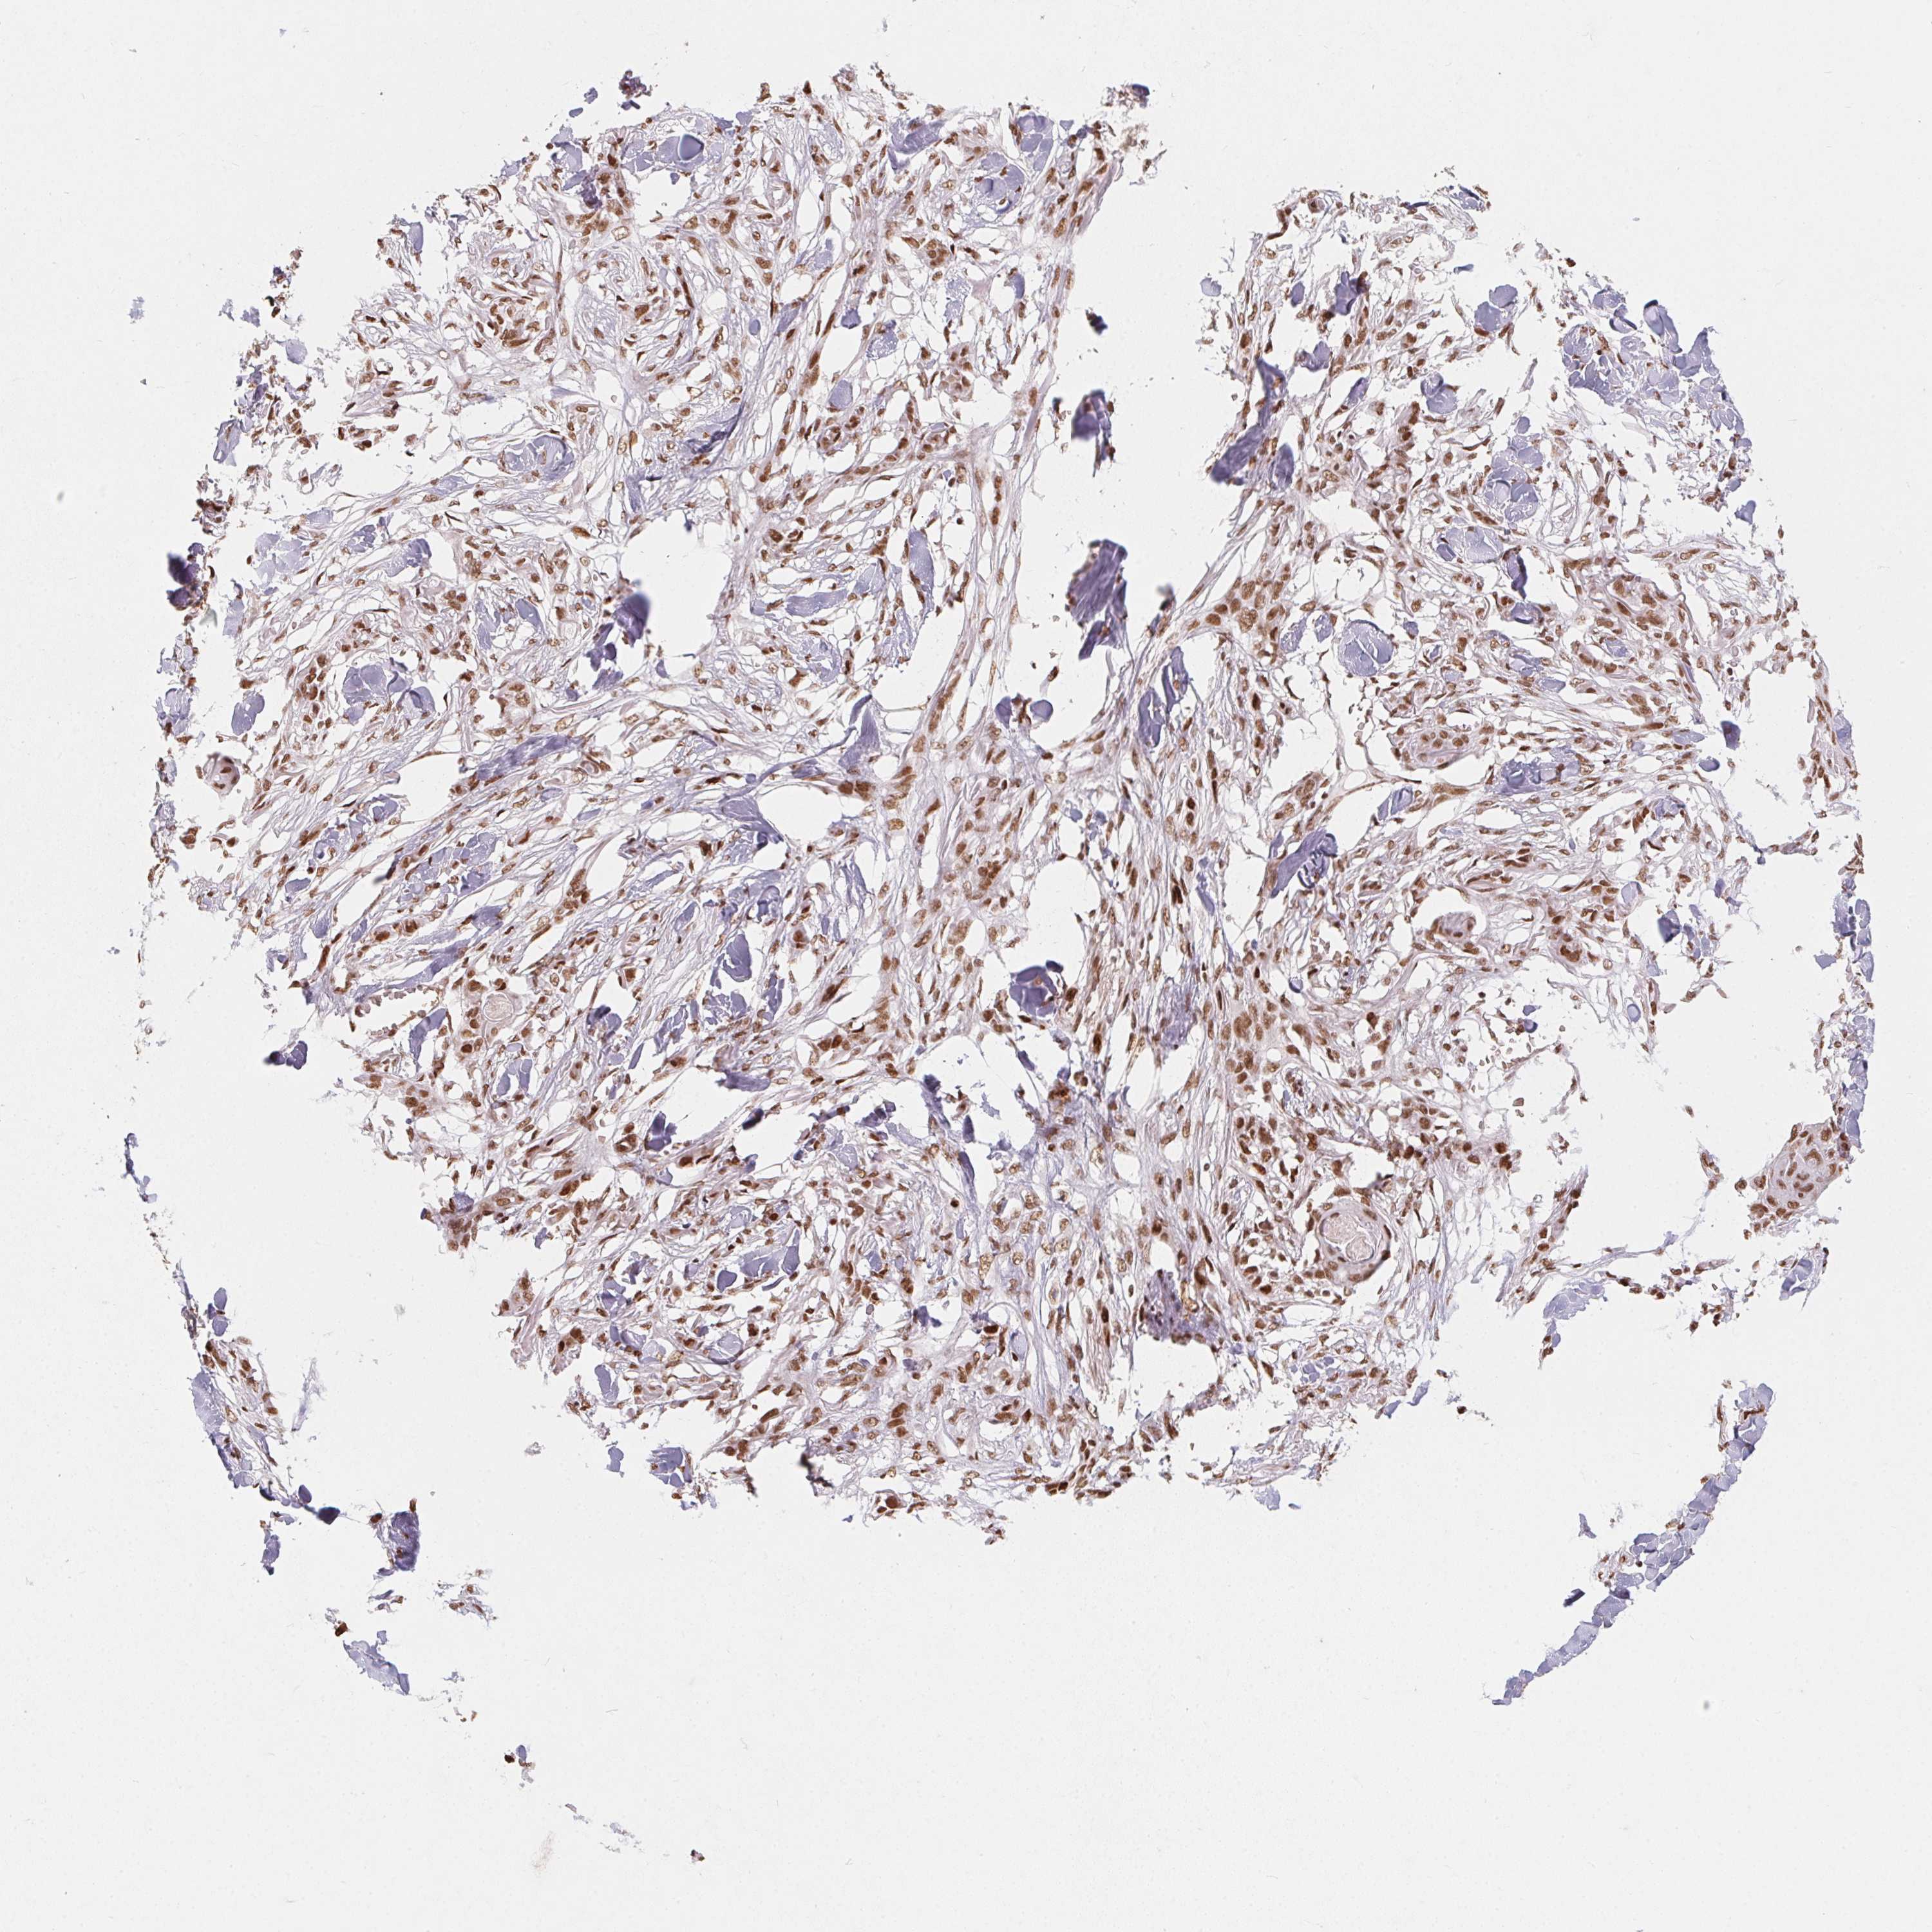

SKIN CANCER - Protein expressioni

A mouse-over function shows sample information and annotation data. Click on an image to view it in a full screen mode. Samples can be filtered based on level of antibody staining by selecting one or several of the following categories: high, medium, low and not detected. The assay and annotation is described here.

Each image is clickable and will lead to virtual microscopy that enables deeper exploration of all samples and also displays staining intensity scores, fraction scores and subcellular localization as well as patient and tissue information for each sample.

Antibody HPA064887

Staining

High

Intensity

Strong

Quantity

>75%

Location

Nuclear

Squamous cell carcinoma, NOS